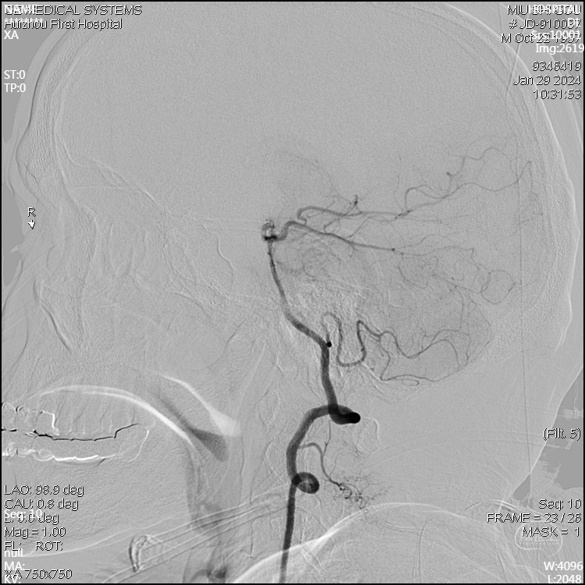

急诊DSA未见畸形血管。

右侧椎动脉正位片

右侧椎动脉侧位片